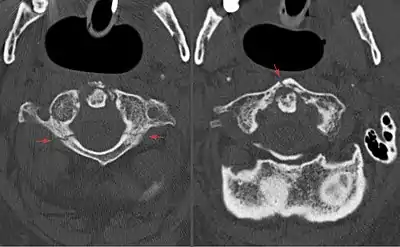

Jefferson fracture

A Jefferson fracture is a bone fracture of the anterior and posterior arches of the C1 vertebra,[1] though it may also appear as a three- or two-part fracture. The fracture may result from an axial load on the back of the head or hyperextension of the neck (e.g. caused by diving), causing a posterior break, and may be accompanied by a break in other parts of the cervical spine.[1]